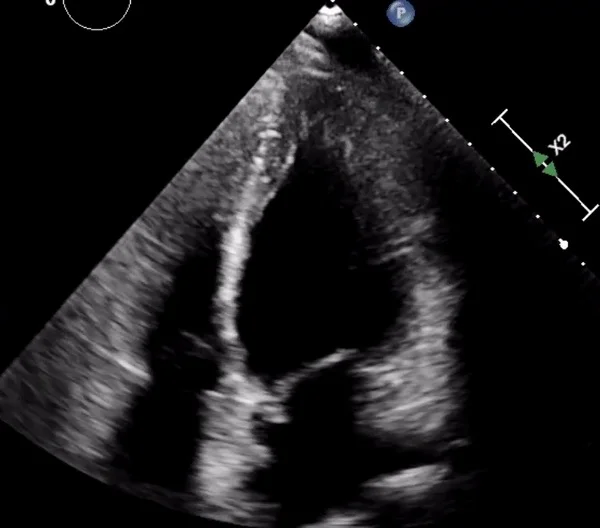

Read MoreOur next Intern Ultrasound of the Month features an incredibly rare case of peripartum reverse (basal-type) Takotsubo cardiomyopathy by Dr. Matt Mullins (PGY1), discovered with point-of-care ultrasound in the ED. Read on to learn more!